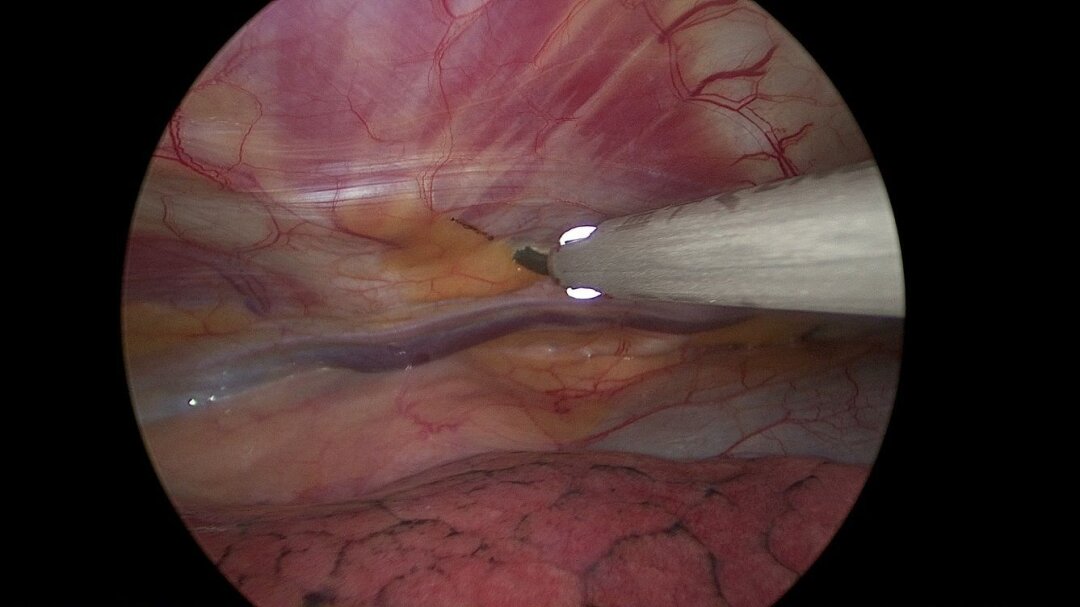

Пациентку оперировала многопрофильная бригада. Этап на органах средостения выполнили торакальные хирурги под руководством заведующего торакальным отделением онкодиспансера Вадима Козлова. Торакоскопически, через небольшие проколы хирург удалил парастернальные лимфоузлы. Ещё 20 лет назад такую операцию делали только при помощи открытого хирургического вмешательства – полностью вскрывая грудную клетку.